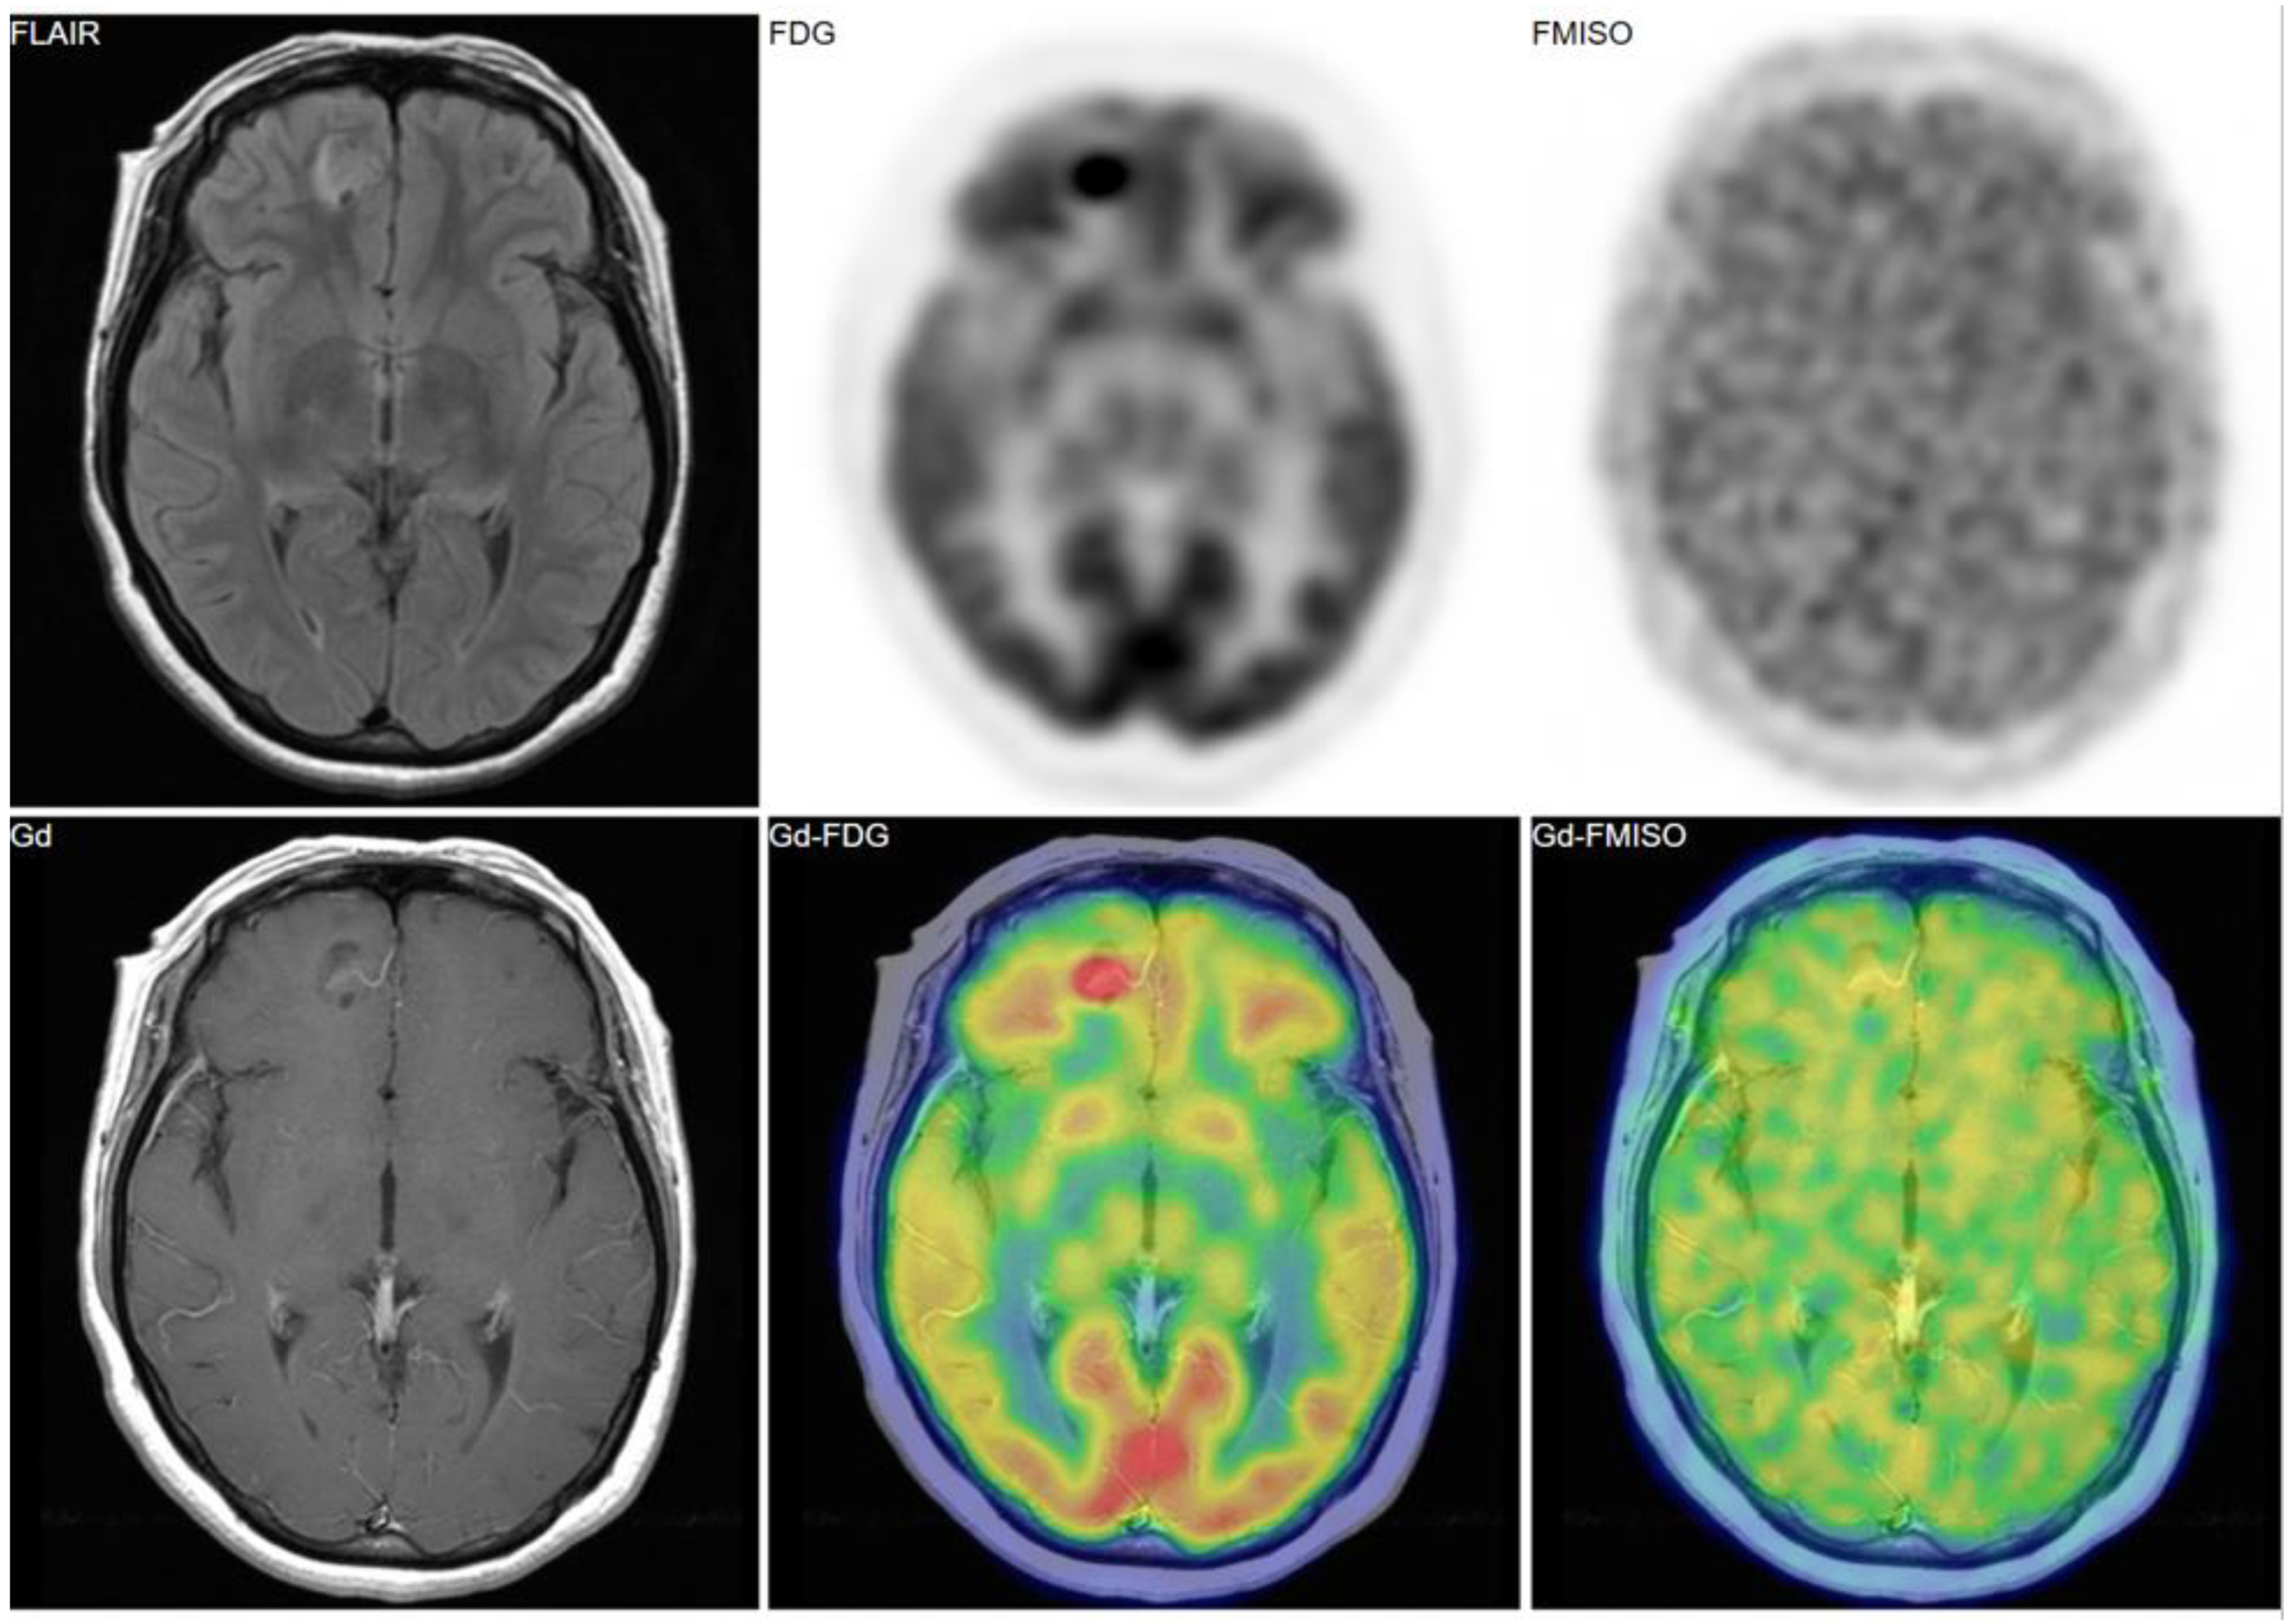

Figure 2, Figure 3 and Figure 4 show some representative cases of low to high grade gliomas. We demonstrated that FMISO has the potential to distinguish glioblastomas (i.e., grade IV gliomas) from less-malignant gliomas (i.e., grade III or lower grade gliomas) [40]. As mentioned above, the oxygen concentration threshold of FMISO uptake is low. Thus, FMISO PET can differentiate tissues with severe hypoxia from those without. Studies using direct needle electrodes suggested that the hypoxic condition of a glioma depends on its degree of malignancy [41,42,43]. We used FMISO PET and FDG PET for the preoperative examination of 23 patients with gliomas of different World Health Organization (WHO) grades [40]. The PET findings were compared with the patients’ post-operative histological findings by neuropathologists. We observed FMISO uptake in the glioblastomas, but not in the less-malignant gliomas (Table 1). In the WHO definition, glioblastoma presents with necrosis in the tumor, whereas lower-grade gliomas do not develop necrosis [44]. It is thus reasonable that only glioblastomas have severe hypoxia (beyond the FMISO threshold) and therefore take up FMISO. We concluded that FMISO PET may be able to clearly distinguish glioblastomas from lower-grade gliomas.

Figure 4. A 69-year-old patient had a tumor in the left medial temporal lobe. Like the case in Figure 3, FMISO uptake was not observed in the tumor, whereas FDG uptake was evident. The pathological diagnosis was anaplastic astrocytoma (grade III).